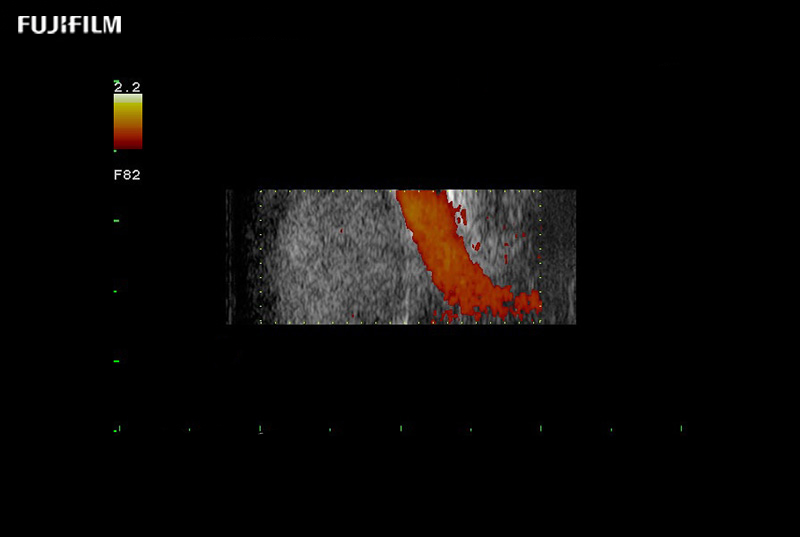

Exclusive 10mm side‐fire linear array transducer with 2.87mm diameter is ideal for real‐time visualization through and behind structures and instant, scalable definition of anatomy and vascularity including the ability to delineate and define tumor margins.

Guidance is the fundamental purpose for all of our surgical ultrasound technology. Fujifilm Healthcare is committed to designing tools that help neurosurgeons navigate inside the human body and provide the necessary information to immediately make critical surgical decisions.